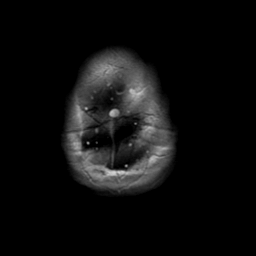

Meningioma, MR Study #2 -- Slice #21

[Home][Help][Clinical] Slice 21